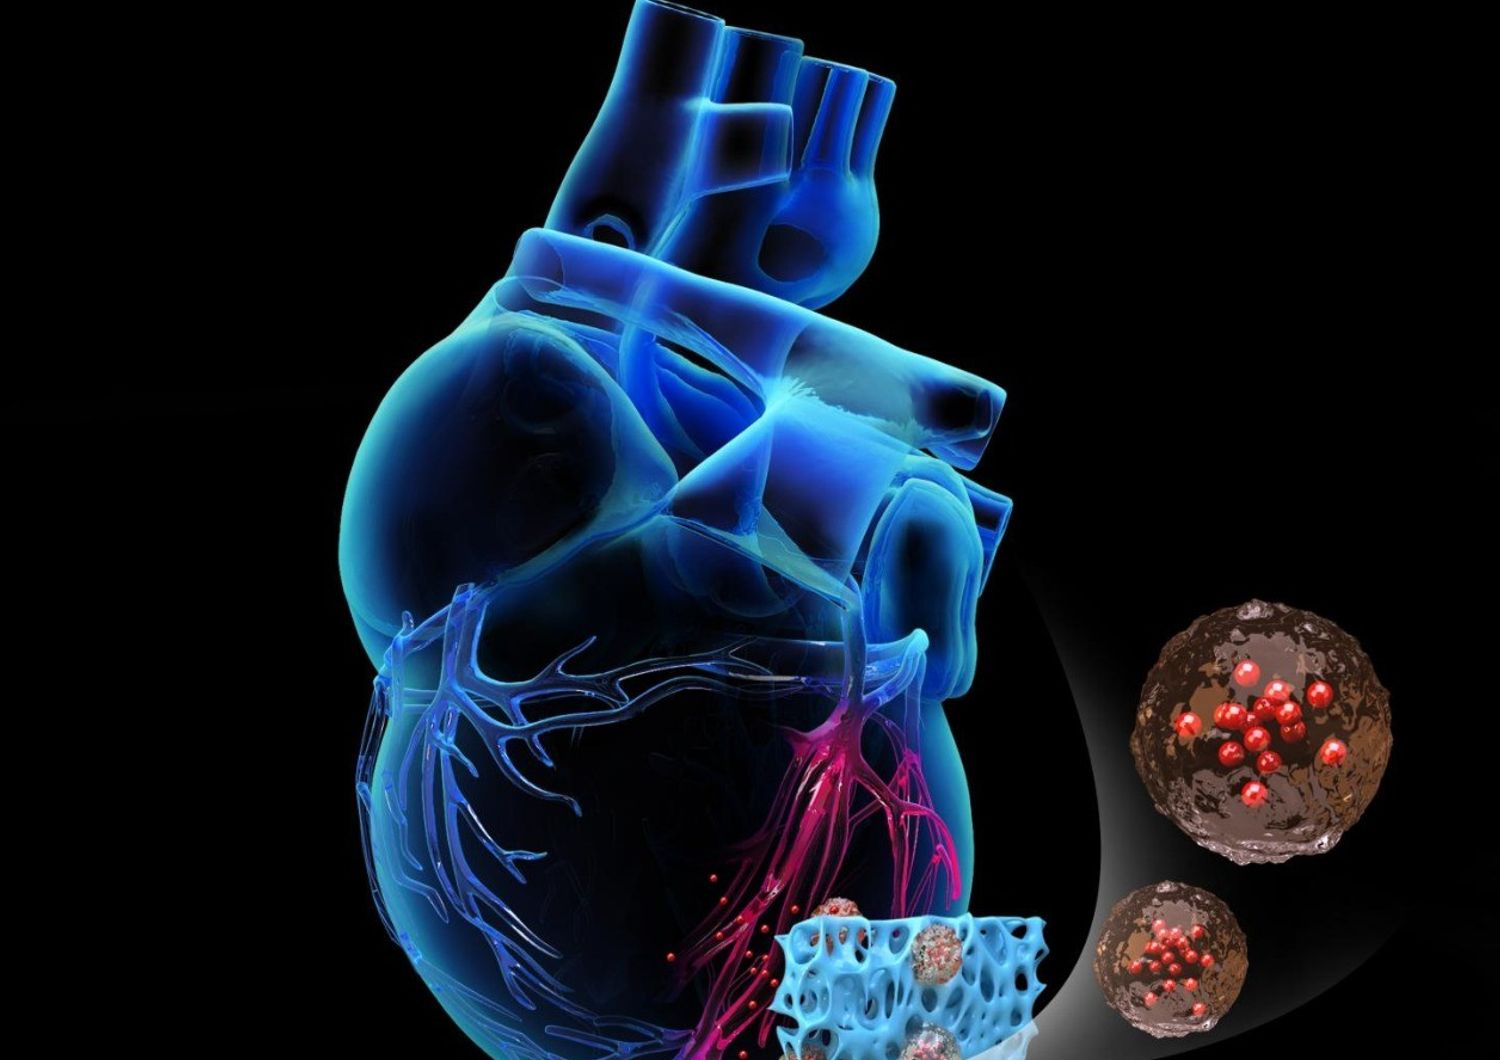

I ricercatori della North Carolina State University hanno sviluppato un cerotto cardiaco artificiale in grado di accelerare la guarigione delle cellule cardiache a seguito di lesioni causate da un infarto. In un articolo pubblicato sulla rivista Science Translational Medicine, gli scienziati hanno descritto questi cerotti come una promettente metodologia di intervento in grado di migliorare il recupero puntuale delle zone lesionate.

"Le soluzioni attuali sono costose e fragili, richiedono molto tempo per la preparazione dato che utilizzano materiale cellulare vivo, il che inoltre aumenta il rischio di insorgenza di tumori e aritmia", spiega Ke Cheng, della NC University. "Abbiamo sviluppato un cerotto cardiaco artificiale che può potenzialmente risolvere i problemi associati all'utilizzo di cellule vive, pur continuando a fornire una terapia efficace sul sito interessato", aggiunge Teng Su, collega e coautore di Cheng. Il team ha costruito il cerotto sulla base di una struttura derivata dal tessuto cardiaco di un maiale.

"Abbiamo poi utilizzato un polimero biodegradabile con fattori di riparazione da incorporare nella matrice di partenza. In questo modo abbiamo ottenuto un cerotto che conteneva tutte le sostanze secrete dall'organismo, ma privo di cellule vive, che potrebbero innescare risposta immunitaria", spiegano i ricercatori, sottolineando che i test effettuati sul modello cardiaco di un ratto hanno mostrato una capacità di migliorare il tessuto per circa il 50 per cento in un periodo di tre settimane, con la presenza di cicatrici ridotta del 30 per cento rispetto agli esemplari in cui non era stato applicato il cerotto.

"Abbiamo condotto uno studio anche sul tessuto cardiaco di un maiale, e dopo sette giorni abbiamo notato una riduzione delle cicatrici di circa il 30 per cento in alcune regioni", prosegue Cheng. "La nostra soluzione può inoltre essere congelata e conservata in modo sicuro per almeno 30 giorni, dato che non sono coinvolte cellule vive. È il primo passo verso una soluzione definitiva per le terapie che richiedono il cerotto cardiaco", concludono i ricercatori.